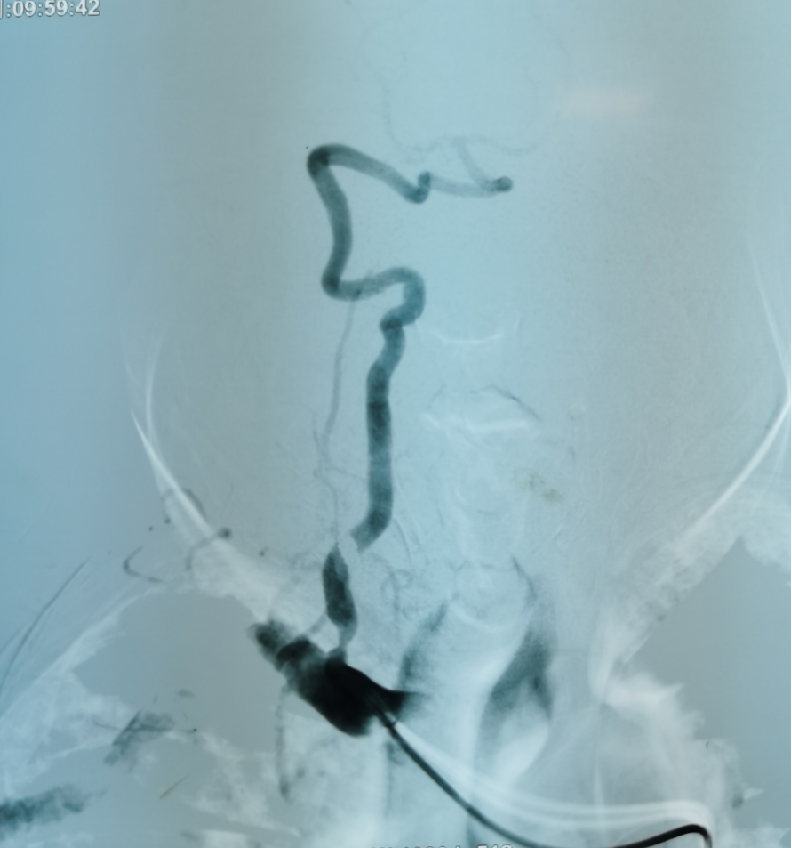

患者赵某某,男,70岁,因突发左侧肢体活动不灵3小时入院,查体:神志模糊,反应迟钝,言语不清,左侧鼻唇沟变浅,口角右侧偏斜,左侧肢体肌力0级,右侧肢体肌力正常,双侧巴氏征阴性。入院颅脑CT示腔隙性脑梗死。主治医师魏华明建议急诊取栓治疗。手术由魏华明主治医师操作,10分钟完善术前准备,5分钟完成脑血管造影,考虑为右侧夹层动脉瘤所致急性期脑梗死,夹层内有急性血栓形成,血栓有进一步加重的可能性,同时夹层有急性撕裂破裂的可能性,病情非常凶险。神经介入团队仅用时30分钟成功为患者实施颈动脉支架植入血管成形术,同时给予尿激酶动脉溶栓,患者左侧肢体肌力立即恢复至3级。术后,经过神经内一科医护团队的精心治疗和严密护理,现患者左侧肢体肌力已恢复至四级。

右侧夹层动脉瘤

颈动脉支架

植入血管成形术